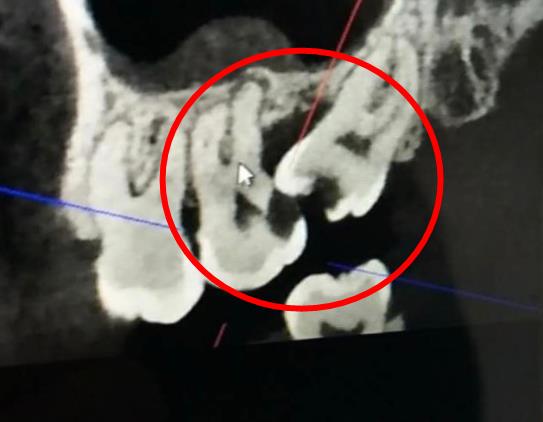

智齒位置不正,造成第二磨牙齲壞

還有一個(ge) 原因是食物長期嵌塞,容易滋生細菌,造成前麵的第二磨牙出現齲壞(見上圖),甚至出現牙周的問題。